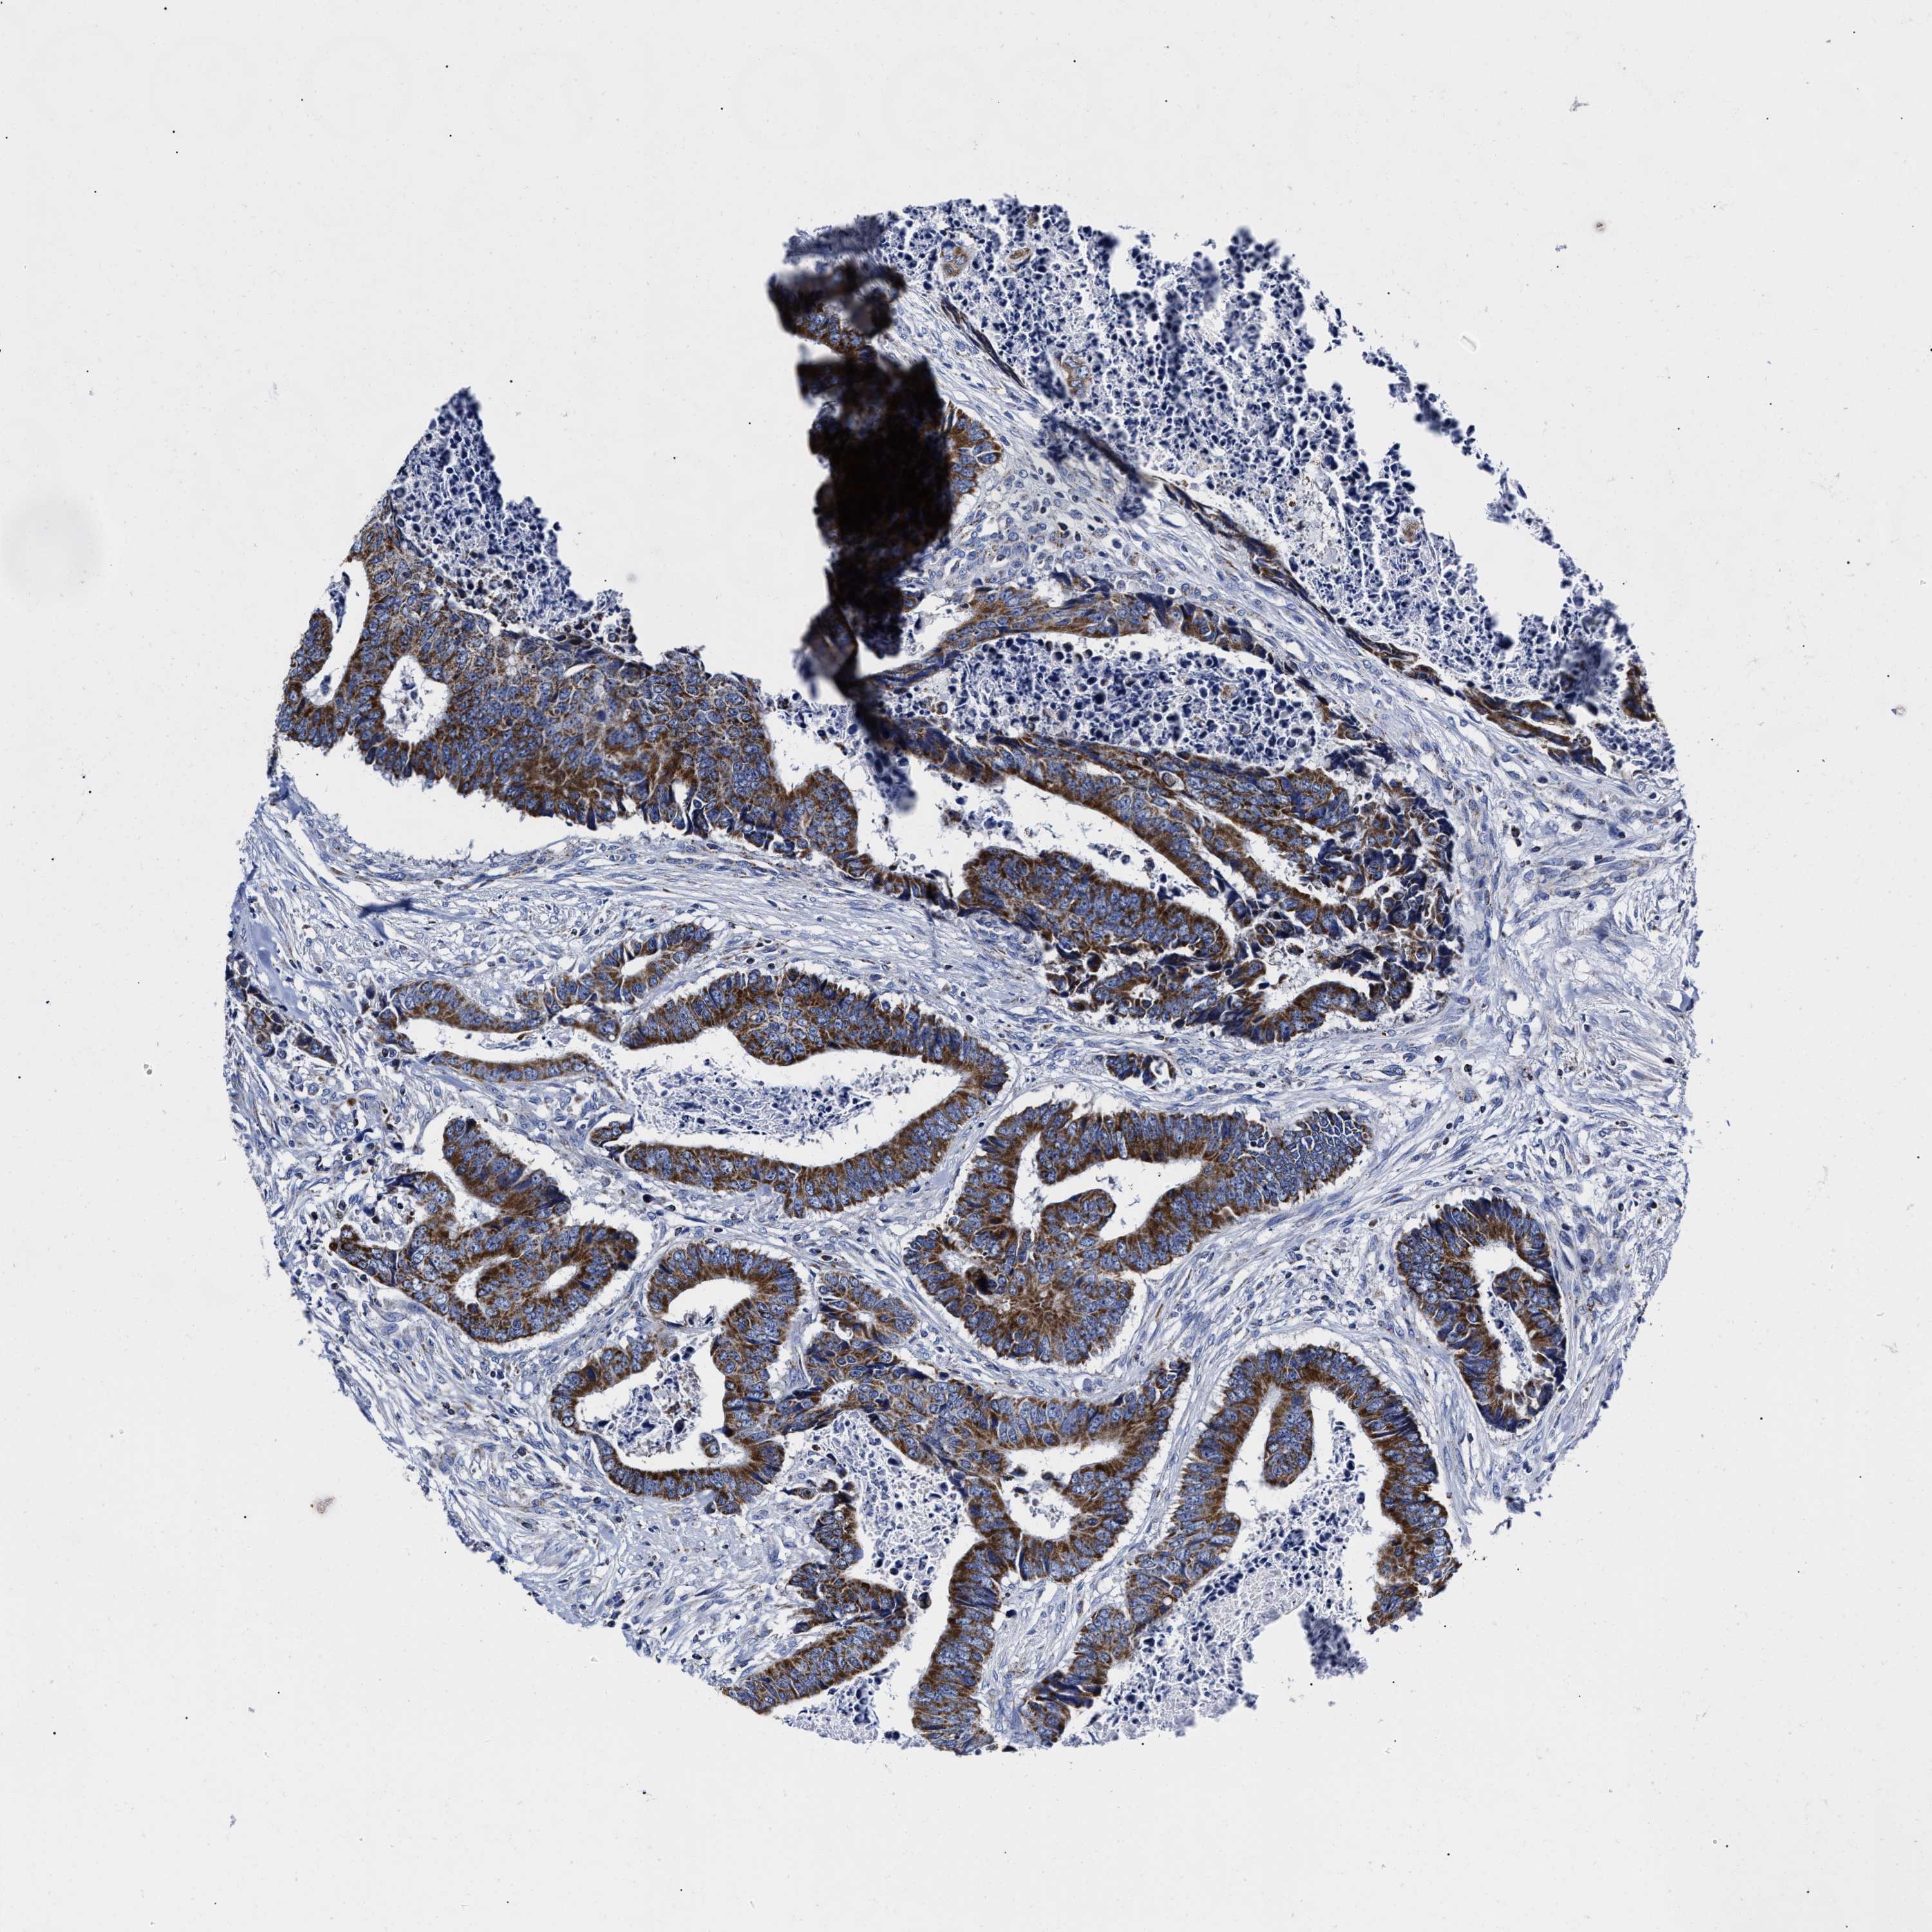

CANCER COLORECTAL CANCER Show tissue menu

Colorectal cancer

Human cancer

Colon adenocarcinoma

Rectum adenocarcinoma